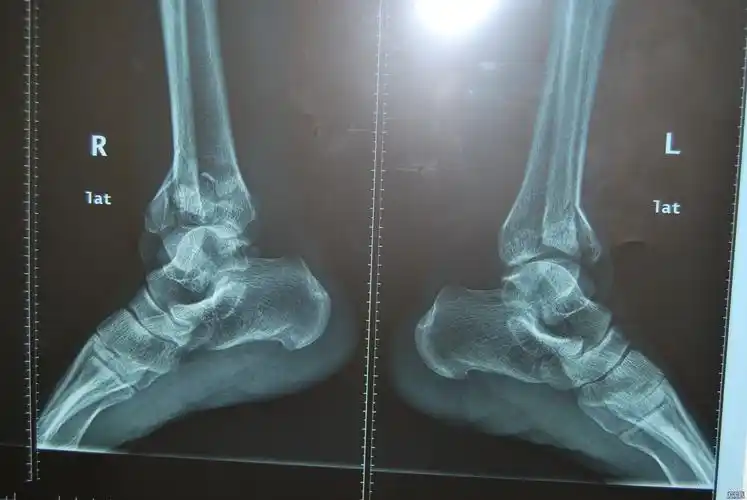

左小腿开放性粉碎性骨折病例汇报

患者男右胫腓骨开放性粉碎性骨折术前[1].jpg

开放性胫腓骨粉碎性骨折结局已经更新

外固定架不开刀治疗胫腓骨远端粉碎性骨折

一例严重胫骨粉碎性骨折,请大家讨论下一步治疗方案? [病例帖]

双胫腓骨下段粉碎性骨折求治疗方案

右胫腓骨下段粉碎性开放性骨折